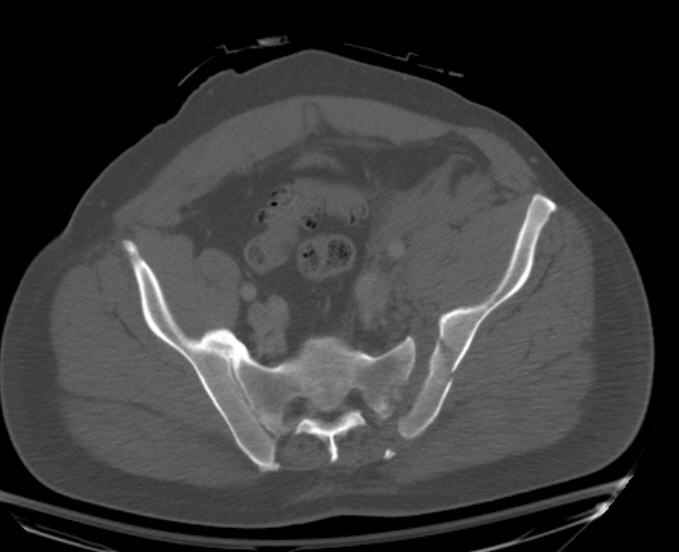

Re: APC III pelvis fx

Request for more images.. Axial and coronal recon (pt in binder.)

Haven't posted initial AP pelvis as it is poor quality, non digital film.